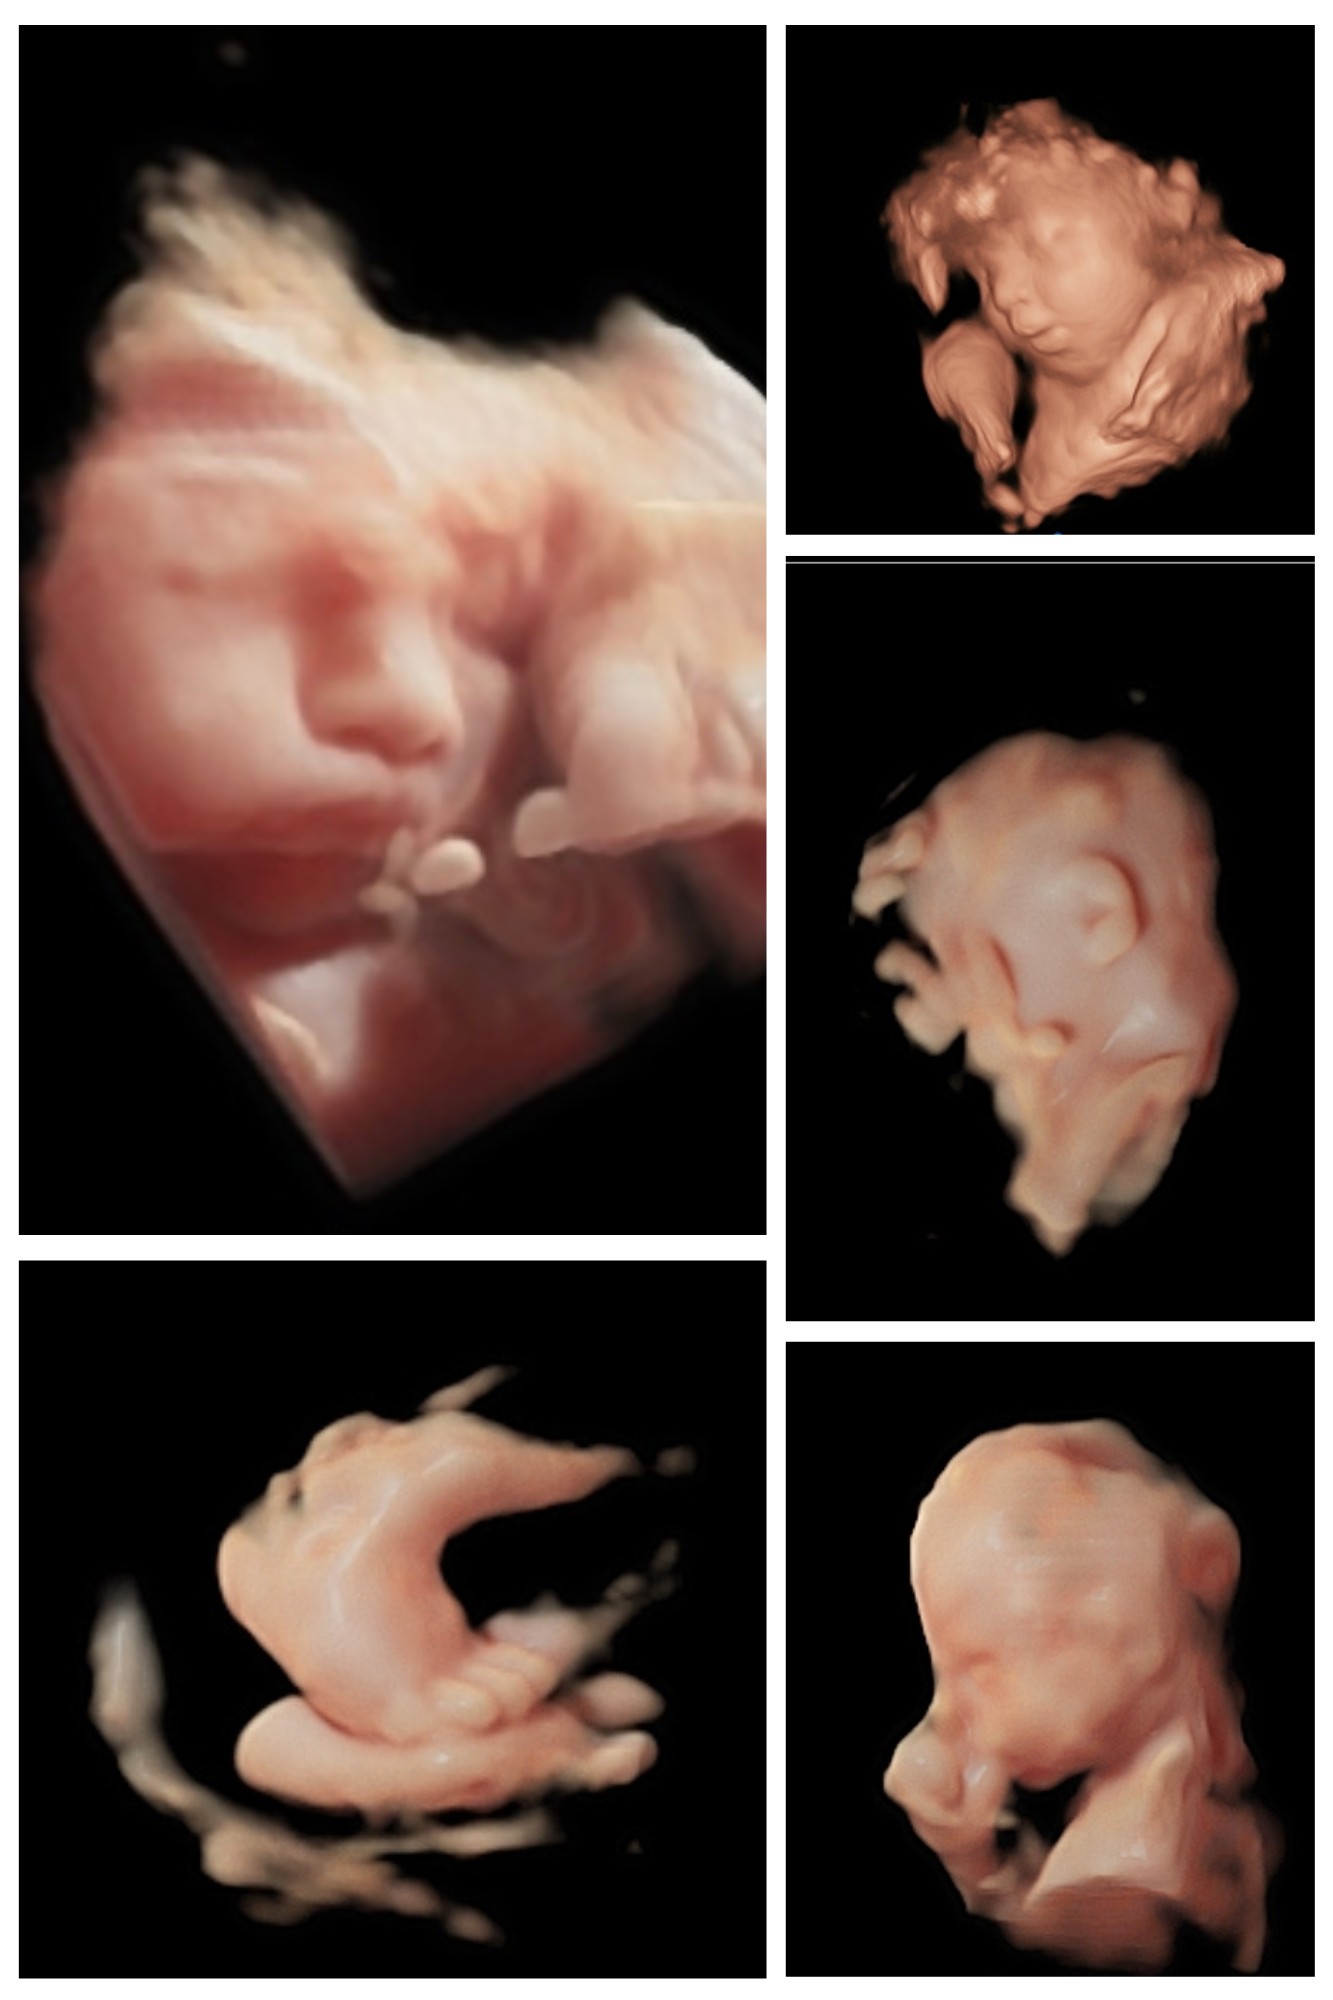

Our elective, non-diagnostic ultrasound services offer expectant families the incredible opportunity to witness the beauty of their baby’s first movements, smiles, and tiny features in amazing detail. Each session is designed to be a joyful, stress-free occasion, enhanced by our thoughtful touches like optional heartbeat-stuffed animals, printed Polaroid keepsakes, and digital images delivered straight to your inbox.

But at New Life Imaging, our mission extends far beyond just ultrasound images. Inspired by Jeremiah 29:11 and Psalms 139:13-16, we believe each baby is fearfully and wonderfully made, uniquely created with a divine purpose. That’s why every session includes not only state-of-the-art technology but also genuine care and compassion.